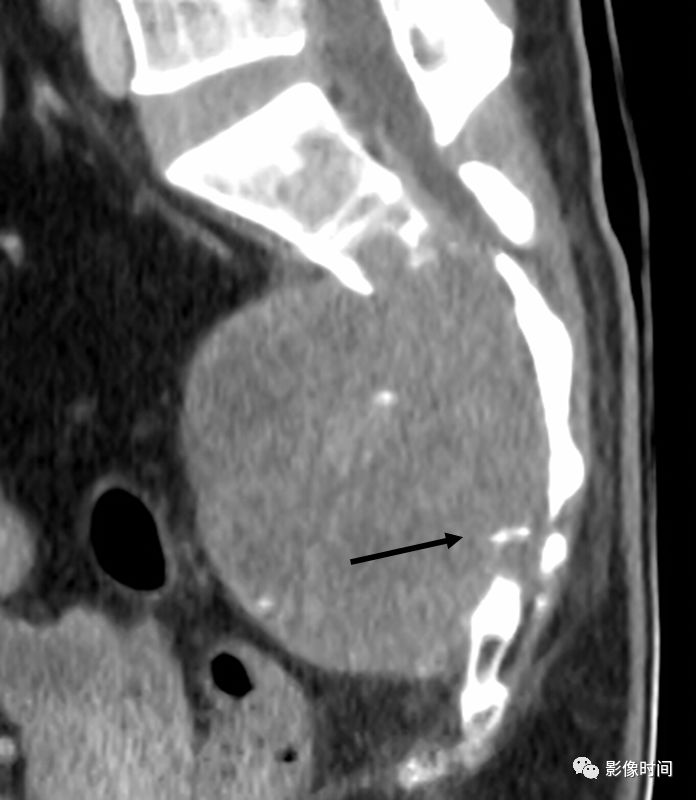

栅栏征(The Palisade sign),也称灯芯绒椎体(corduroy vertebra)或灯芯绒征(corduroy sign)

脊椎椎体因病变导致骨小梁吸收、稀疏,为满足承重需要,存留的纵向骨小梁粗大;粗大骨小梁间以细条状密度减低区,形成栅栏样影像,故称栅栏征或灯芯绒椎体。

栅栏征最常见于血管瘤,以单个脊椎居多;骨质疏松如泛发性骨质增生症、老年性骨质疏松等亦可呈现此类表现,一般见于下胸椎、上部腰椎的多个椎体,只是伴有普遍的骨密度减低。有时自颈椎至腰椎全部椎体均出现栅栏征。栅栏征主要见于椎体。

病例 1,脊柱血管瘤。胸腰椎 CT 冠状位、矢状位 MPR 重建示胸 12 椎体松质骨密度降低,其中可见粗大骨小梁呈栅栏状。

圆点征指的是在横断面图像上,椎体骨松质呈粗大网眼状改变,残留骨小梁增粗呈稀疏排列的多发粗点状高密度影。此征象多提示脊柱血管瘤。

典型病例

胸椎血管瘤。A.CT 横轴位骨窗示椎体右侧部骨小梁稀疏粗大,呈圆点征;B. 矢状位 MPR 图像呈现栅栏征。